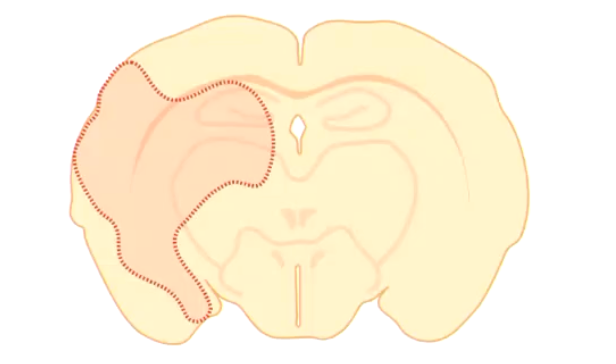

What are the characteristics of Lissencephaly?

• Slow or failed neuronal migration of brain neurons = Lack of development of the surface folding of the cerebrum

Characterized by a small, smooth-appearing cerebrum with rudimentary or absent gyri (agyria) and sulci.

What are the signs and causes of lissencephaly?

• Signs:

• Cognitive dysfunction

• Abnormal behavior

• Seizures

• Causes:

• Suspected inherited condition in Lhasa Apso (common)

• Intrauterine hypoxia (human)